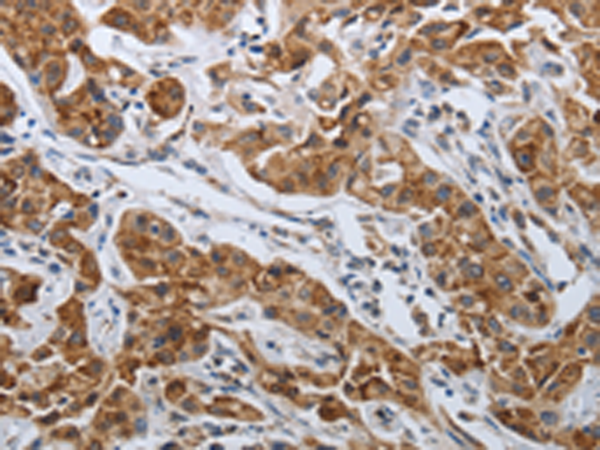

分类: 科研抗体货号: P11131别名: SELS; VIMP; ADO15; SBBI8; SEPS1; AD-015应用: IHC反应种属: Human, Mouse, Rat